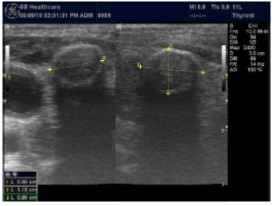

The reported prevalence of nodular thyroid disease depends on the population studied and the methods used to detect nodules 16. Our study population is unique as it is composed entirely of ESKD patients. We also used ultrasound as a method of detecting thyroid abnormalities. In our study the prevalence of thyroid nodular pathology as detected by ultrasound was found to be 57.6% mirror image what reported in the literature as it has been reported that nodules found on ultrasonography suggest a prevalence of 19 to 67%17, 18; and in other publications it has been reported to range from 50% to 70% 7, 8. Figure 3A below shows an Ultrasound detected thyroid nodule.

High-resolution ultrasonography (USG) is the most accurate and cost-effective method for evaluating and observing thyroid nodules 3. Although there is some overlap between ultrasound appearance of benign and malignant nodules, certain USG features are helpful in differentiating the two. Iso-or hyper-echogenicity of the thyroid nodule in conjunction with a spongiform appearance is the most reliable criterion for benignity of the nodule on gray-scale ultrasound, Figure 4A. Other features like nodule size <1 cm, width > length, presence of hypoechoic or hyperoechoic halo around the nodule, Figure 4A and Figure 4B, caused by fibrous capsule compressing thyroid tissue, and coarse/curvilinear calcification are less specific but may be useful ancillary signs4 ,6. "Ring down" or "comet-tail" artifact or sign is typical of benign cystic colloid nodule, Figure 520. Perinodular flow or spoke-and-wheel-like appearance of vessels on color Doppler examination is characteristic of a benign thyroid nodule. However, this flow pattern may also be seen in thyroid malignancy. A complete avascular nodule is very unlikely to be malignant 4.

Figure 4B.Isoechoic nodule with Hyperechoic rim